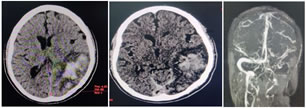

CASE 1-

Figure 1: 50Years old male patient presented with headache, loss of memory and irrelevant speech since 2days

A: Axial plain CT shows hyperdense superior sagittal sinus with left temporo-parietal hemorrhagic infarct; B: Axial contrast enhanced CT shows empty delta sign with non opacification of left transverse sinus; C: MR Venography confirms thrombosis of distal segment of superior sagittal sinus and left transverse sinus. Hounsfield unit (HU)-68 ; Haematocrit (HCT)-42.2% ; HU: HCT=1.61